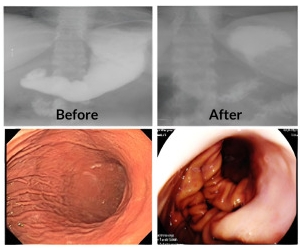

POSE 2.0胃鏡縫胃是國際公認的新一代內視鏡減重手術,特色是一種經口進行、無需開刀,全程由專利內視鏡設備操作,透過「全層縫合技術」將胃壁折疊,減少胃容量70%,讓食物很快產生飽足感,有效降低食慾,不容易感到飢餓。

醫師使用一種獨特的 「雪靴夾」裝置,在胃體中段(包含胃底及胃體部)進行全層胃壁縫合,創造出類似胃皺襞(folds)的結構,將胃部組織摺疊起來,並進行穩固的固定,術後胃容量減少70%。